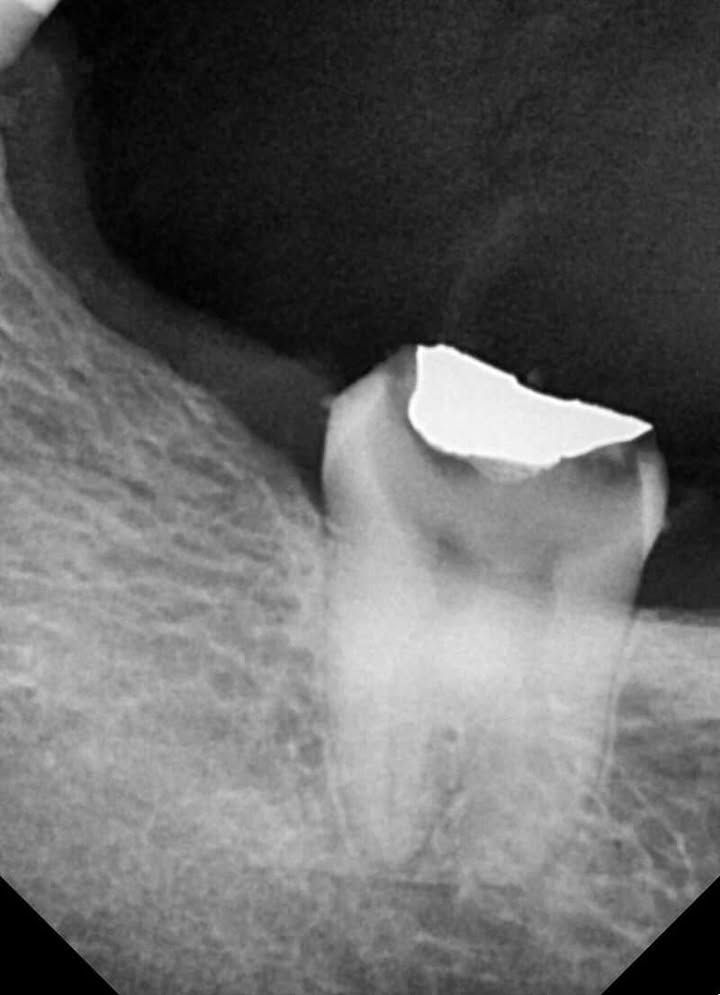

Tooth: #47

Diagnosis: Symptomatic Irreversible Pulpitis

Case Difficulty: Advanced Case

This advanced endodontic case involved Tooth 47 diagnosed with symptomatic irreversible pulpitis. The mesial canals were severely constricted with extreme curvatures, presenting a significant challenge in achieving patency and managing the high risk of apical blockage.

- Removal of Previous Restoration

The old restoration was completely removed to allow proper access. - Coronal Preflaring